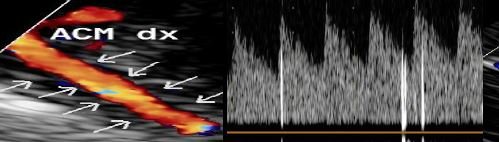

Master di ECOGRAFIA TRANS-CRANICA in Cardiologia

Corso Teorico-Pratico di Ecografia Trans-Cranica con applicazione cardiologica